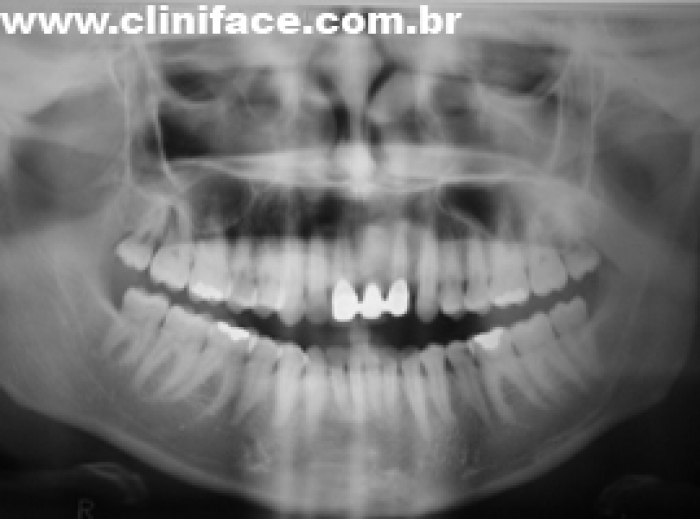

Raio X de 03 anos e 08 meses de controle